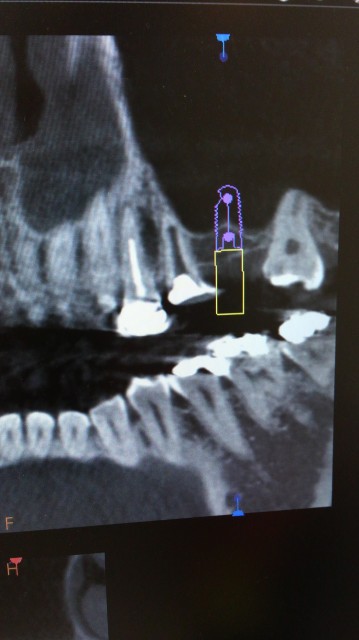

下のレントゲンの方はインプラント希望ですがCTでシュミレーションしたところ、

骨がかなり足りません。

ソケットリフトをして、同時にインプラントを入れました。

ソケットリフトなのでインプラントを入れるために作った穴から骨移植をしています。

普通のレントゲンで診るとうまくいっているように見える症例でも、CTで診てみるとインプラントの一部に移植骨が全く行き渡っていないこともあります。